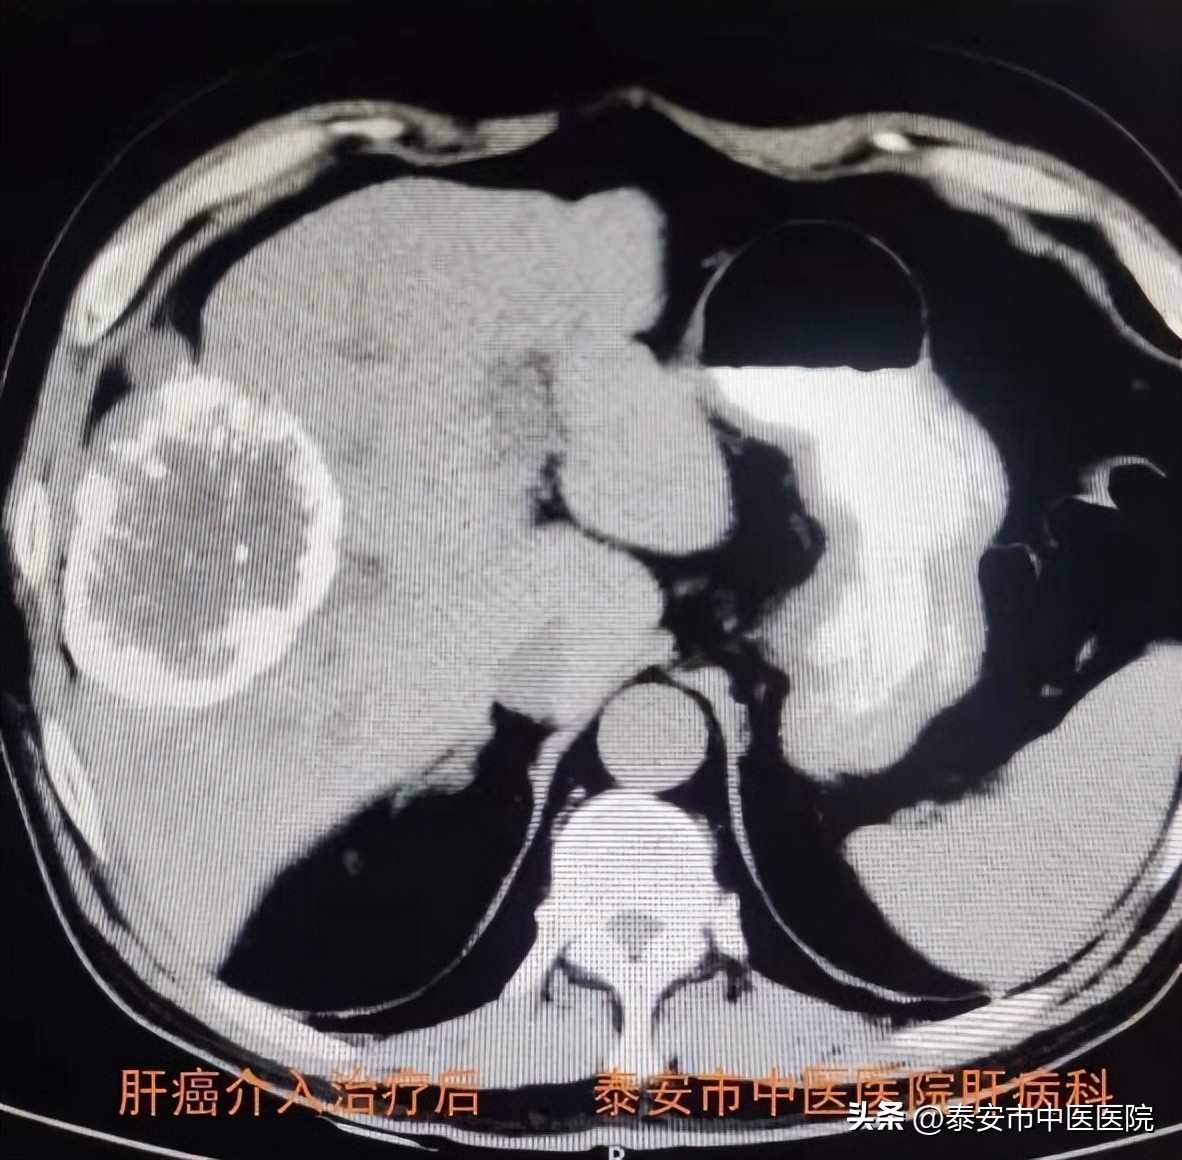

3.肝癌介入治疗

借助医院引进的 Philips最新一代霓彩系列大平板数字减影血管造影机(DSA) ,与介入科合作开展肝癌介入治疗。在数字减影血管造影机下,选择插管至肿瘤供养血管内,进行肝动脉灌注化疗(TAI)、肝动脉栓塞(TAE)、肝动脉化疗栓塞(TACE)等治疗,是控制肝癌生长及联合系统治疗的主要手段之一。